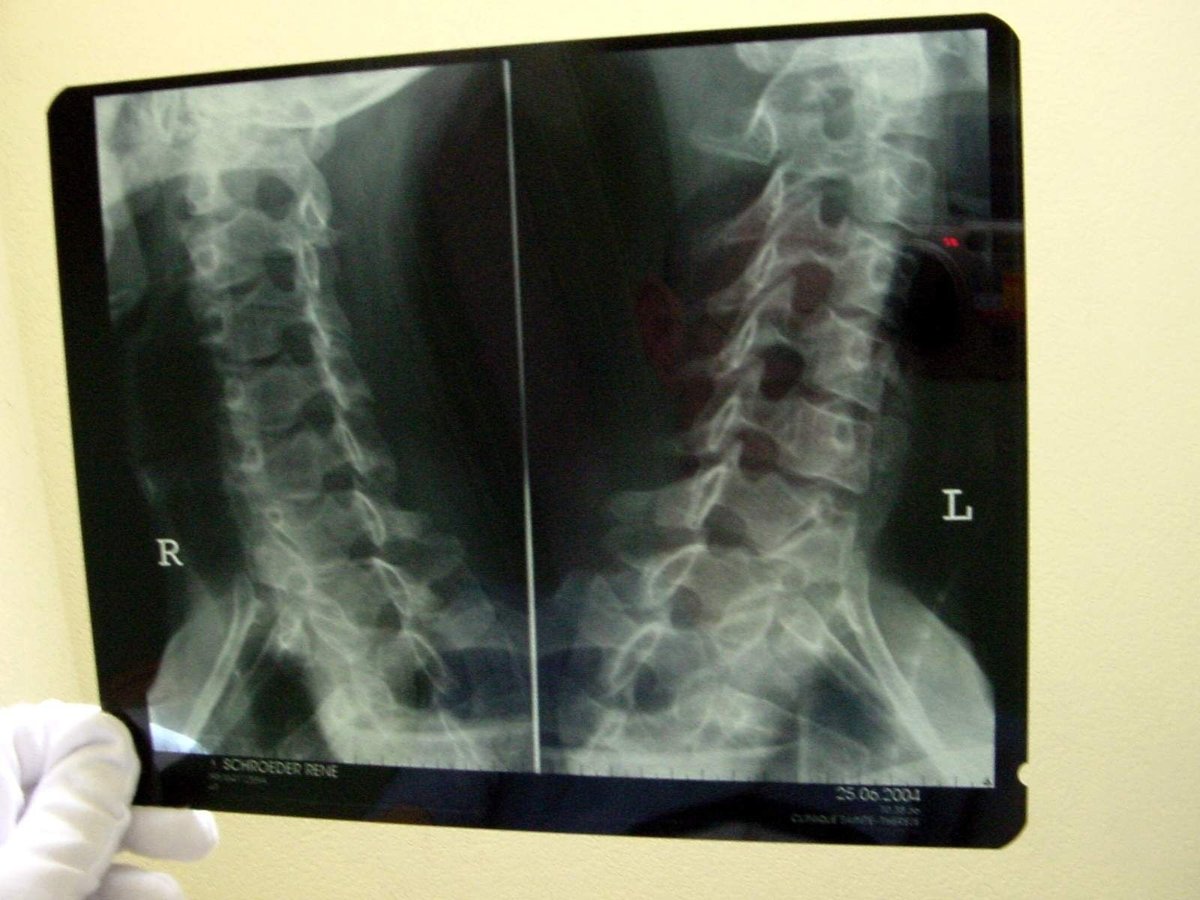

La recuperación ante estas lesiones, al margen del tipo, requiere el reposo durante aproximadamente 3 días o 72 horas e inmovilización del cuello mediante la colocación de un collarín semirrígido. Los profesionales sanitarios, como aquellos de los que dispone Sanitas Consulting, serán los encargados de realizar las distintas radiografías, escáneres y pruebas neuronales necesarias para realizar un diagnóstico certero y rápido de las consecuencias del latigazo en el cuello. Para recuperar la movilidad y la musculatura de la zona, tras el reposo, es posible se tengan que tomar antiinflamatorios o relajantes musculares y que se requieran ejercicios de rehabilitación.